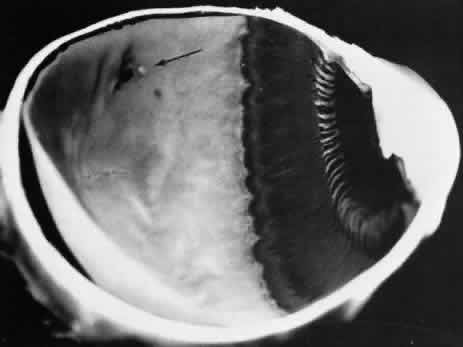

Retinoschisis associated with a bullous architecture and prominent reticular cystoid degeneration has been termed reticular degenerative retinoschisis. Reticular degenerative retinoschisis can be distinguished from typical degenerative retinoschisis by the large extent of retinal involvement, a round or ovoid configuration with bullous elevation of the extremely thin inner layer, and an irregular, pitted outer layer (Figs. 20 and 21). Typical cystoid degeneration is always present anterior to the schisis; reticular cystoid degeneration is usually prominent at some site in the involved eye. Blood vessels coursing through the inner layer give it an arborizing reticular pattern on contact lens biomicroscopy. The intraretinal cavity is optically empty; the outer wall is irregularly excavated to produce a pocked or honeycomb appearance. Round or ovoid holes are often present in the outer retinal layer; they are single or multiple, frequently large, and usually associated with a rolled posterior edge.13

Fig. 20. Reticular degenerative retinoschisis. Note reticulated, highly elevated, inner wall with a conspicuous delicate vascular pattern. Radial columns of the retina are completely disrupted within the region of bullous elevation, and the retinoschisis extends posterior to the equator. (× 18.)

Microscopic sections demonstrate the extremely attenuated, blood vessel-containing inner layer composed of the internal limiting membrane and remnants of the nerve fiber layer (Fig. 22). The honeycomb appearance of the outer layer corresponds to irregular excavations. In some areas, the outer layer is made up of outer plexiform, outer nuclear, external limiting, and rod and cone layers; in other areas it is reduced to only the external limiting and the rod and cone layers; round or ovoid holes may be present (Fig. 23).

Reticular degenerative retinoschisis is evident in 1.6% of adult patients, is bilateral in only 16% of these, and thus is noted in 0.95% of adult eyes (see Table 3). The lesion is found most commonly in the inferior temporal quadrant. A band of typical cystoid degeneration always separates the schisis from the ora serrata; the schists usually reaches the equator and often extends appreciably into the posterior retina.

On contact lens biomicroscopy, many retinal blood vessels present irregular contours, telangiectases, occluded segments, and microaneurysms. Between these vessels, the inner wall has a finely textured appearance and variable white, glistening particles on the vitreous side. The outer retinal wall is best seen when scleral depression produces a “white with pressure” phenomenon and reveals the honeycomb appearance. The retinal pigment epithelium often has a granular, salt-and-pepper appearance, and outer-layer retinal breaks are common. These breaks are particularly likely near the anterior and posterior margins of the schisis.